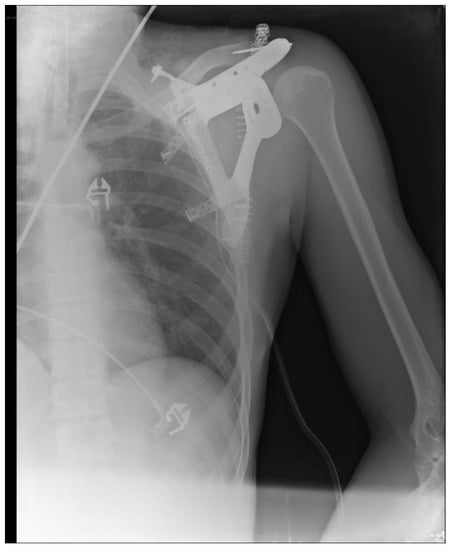

2.3. Surgery

2.4. Follow-Up